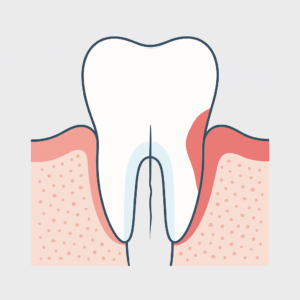

歯の根にヒビが入ると、周囲の組織が炎症を起こし、ポケットが短期間で深くなることがあります。特に痛みがなく進行することも多いため、メインテナンス時のチェックが大切です。

なぜポケットが急に深くなるのか

歯の根に小さなヒビが入ると、そこから細菌が入り込み、

その周囲の骨や歯ぐきの組織が溶けてしまうことがあります。

この現象が進むと、ある日突然、6mm以上のポケットができることがあります。